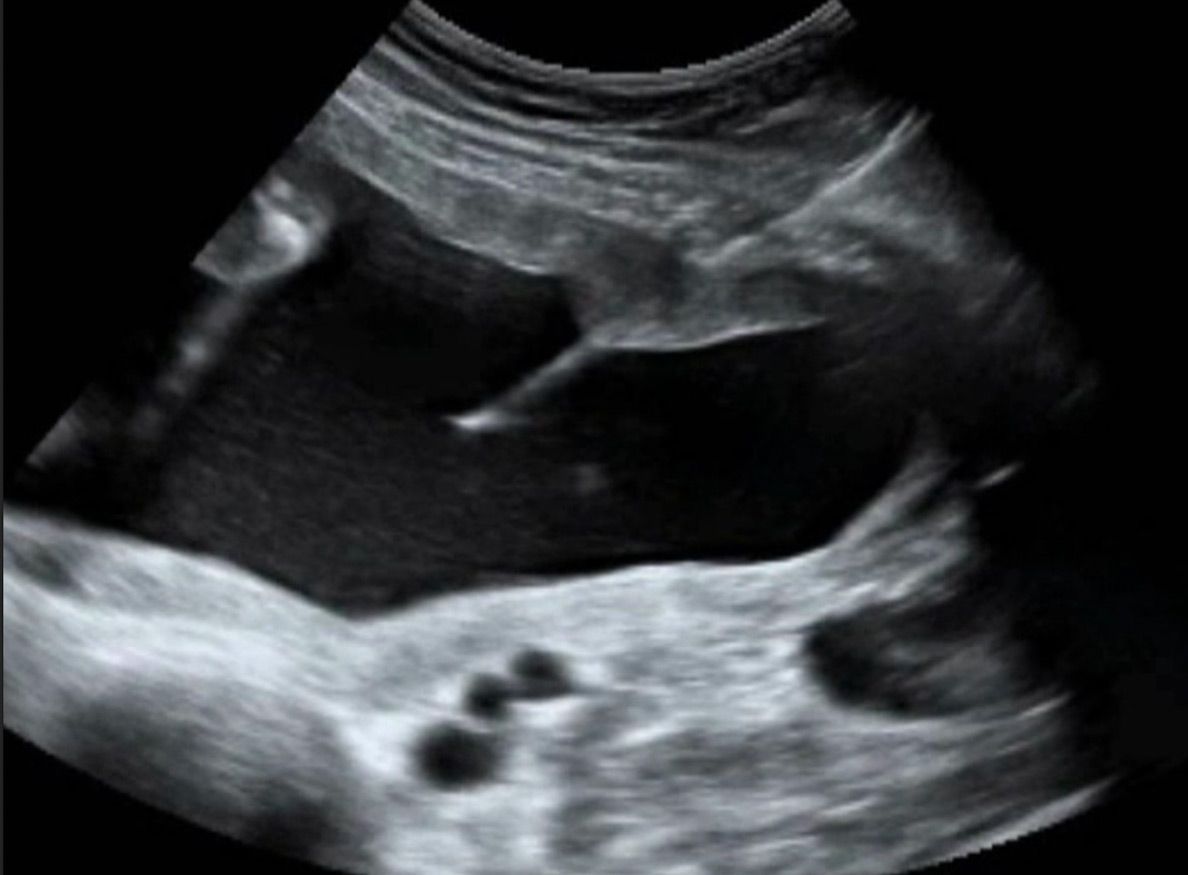

Die Punktion erfolgt im Untersuchungszimmer. Zunächst die Bauchhaut desinfiziert und ein steriles Tuch über die Beine gelegt. Mit der Nadel wird dann die Fruchthöhle punktiert. Der Untersucher verfolgt den Verlauf der Nadel mittels Ultraschall und kann auf diese Weise die korrekte Position der Nadel bestätigen. Nach korrekter Platzierung der Nadel, wird etwa 15ml Fruchtwasser entnommen. Dieses wird innerhalb von 24 Stunden wieder nachgebildet.

Die gesamte Punktion dauert etwa eine Minute, und wird von den meisten Patientinnen als nicht schmerzhaft beschrieben. Das Fruchtwasser wird an Humangenetik zur weiteren Diagnostik weitergeleitet. Abschließend erfolgt nochmals eine Ultraschallkontrolle.